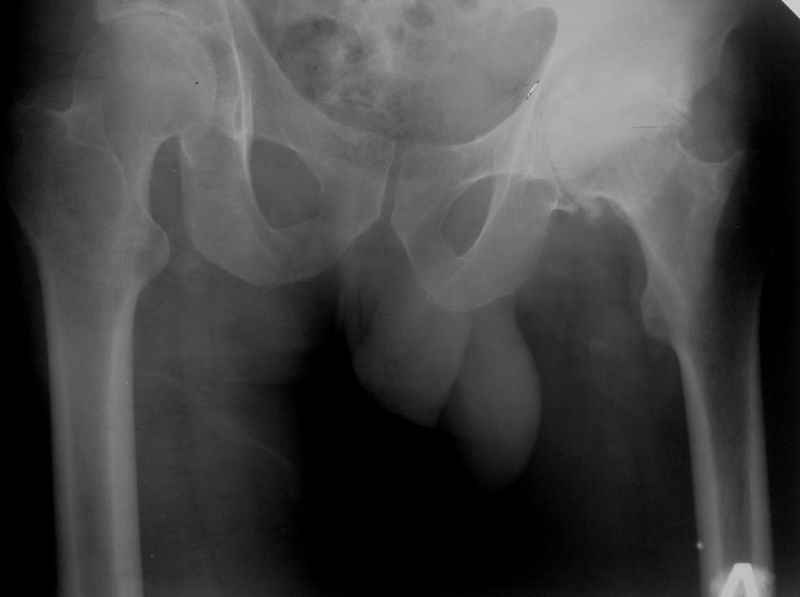

Исходный сустав в приложении.

Какой доступ использовали? Насколько он был травматичен? Я бы дождался полного заживления раны и через пару месяцев выполнил ревизию с заменой чашки, вкладыша и, скорее всего, головки. По снимку похоже что установлена короткая головка, после переустановки чашки в правильную позицию, скорее всего, потребуется стандартная или даже плюсовая.

Доступ по Хардингу. Головка действительно S.

Чашка конечно же Variocup(Varioloc - ножка). После "погружения" чашки головку скорее всего придется менять на M или L.